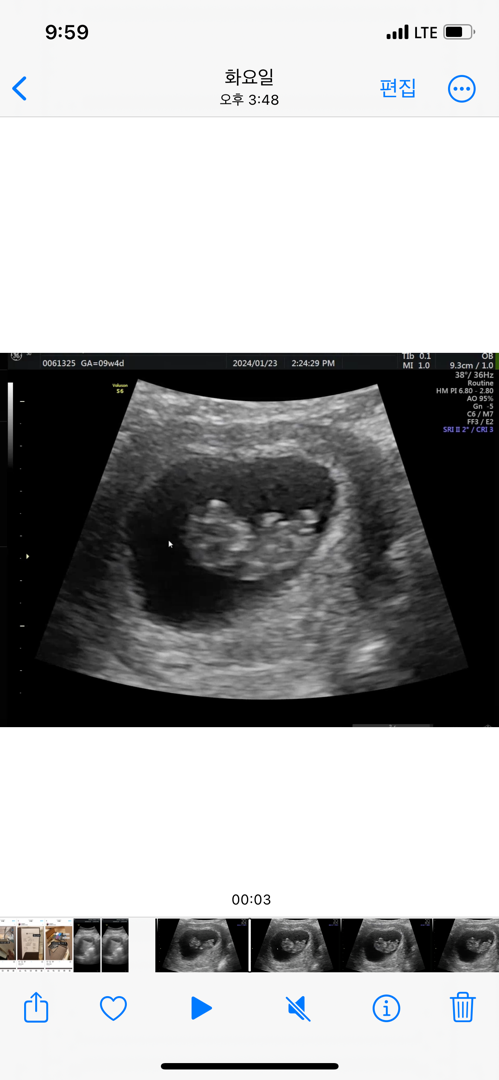

10주인데 각도법 가능할까요?ㅎㄹ

측면입니다ㅎㅎ

이걸로는 알수없어요… 척추랑 엉덩이가 보이는 옆모습이어야한대요